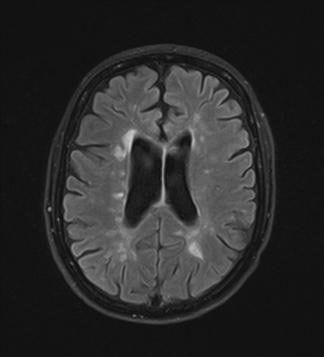

Die Diagnose der Multiplen Sklerose basiert auf folgenden Untersuchungen: In den meisten Fällen ergibt sich durch eine sorgfältige Befragung und neurologische Untersuchung des Patienten bereits ein hinreichender Verdacht auf das Vorliegen der Erkrankung. Zur Bestätigung wird dann eine Magnetresonanztomographie des Gehirns und des Rückenmarks, eine Lumbalpunktion (zwecks Untersuchung des Nervenwassers – sog. Liquor – auf entzündliche Veränderungen, den sog. oligoklonale Banden) und elektrische Untersuchungen (visuell evozierte Potenziale, VEP) durchgeführt. Dies alles sowie diverse Blutuntersuchungen dienen dem Ausschluss anderer Erkrankungen, die ähnliche Beschwerden verursachen können. Allerdings kann keine dieser Untersuchungen alleine die Diagnose MS sichern, manchmal bleibt es am Beginn bei dem Verdacht und erst im weiteren Verlauf und einer Beobachtungszeit von mehreren Monaten wird die Diagnose sicher.